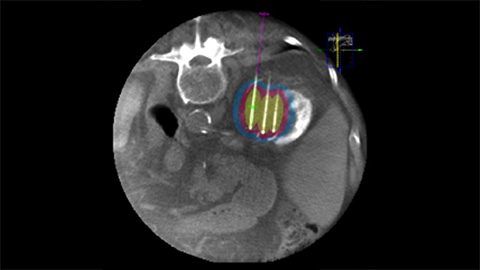

Dual View allows the overlay of a pre-procedure 3D image (CT/MR/PET-CT) on an intra-procedure 3D CBCT to better visualization the lesions and access critical input for needle planning [8].

XperGuide Ablation provides comprehensive assistance for treatment planning and live needle guidance. It offers unique Parallax Correction to plan needle trajectories for off-center lesions [9].

XperGuide Ablation displays the virtual needle path to assist in multiple needle planning. It shows needle characteristics such as ablation zone/isotherm to confirm complete tumor coverage prior to ablation.